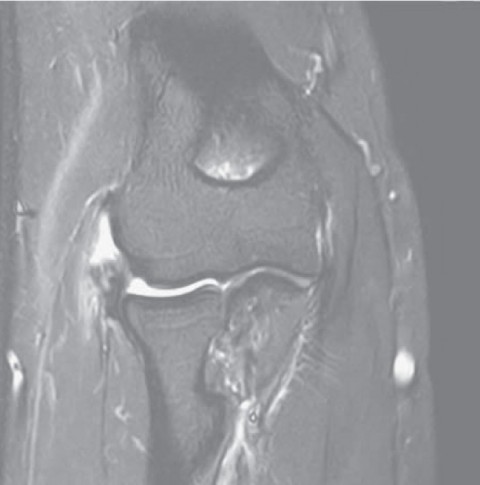

Bei Patienten, bei denen die Strecksehne eine erhebliche Schädigung (einen Riss) aufweist, stellt sich die Frage nach der idealen Therapie, wenn die nicht operativen Ansätze versagt haben. Diesem Thema widmete sich unser Team, zusammengesetzt aus den Abteilungen Schulter- und Ellbogenchirurgie, Rheumatologie und Lehre, Forschung & Entwicklung. Das Team hat 20 Patienten mit langanhaltenden Tennisarmbeschwerden und gerissener Strecksehne mittels Operation behandelt und die Ergebnisse ausgewertet. Die Schlussfolgerung ist, dass bei Patienten mit chronischen Tennisarm-Beschwerden zu empfehlen ist, mittels MRI-Aufnahme zu prüfen, ob nicht eine gerissene Strecksehne der Übeltäter ist. Denn in diesem Fall kann eine Operation die langeersehnte Linderung bringen. Vorausgesetzt ist eine durch Physiotherapie begleitete Nachbehandlung von ca. drei Monaten.